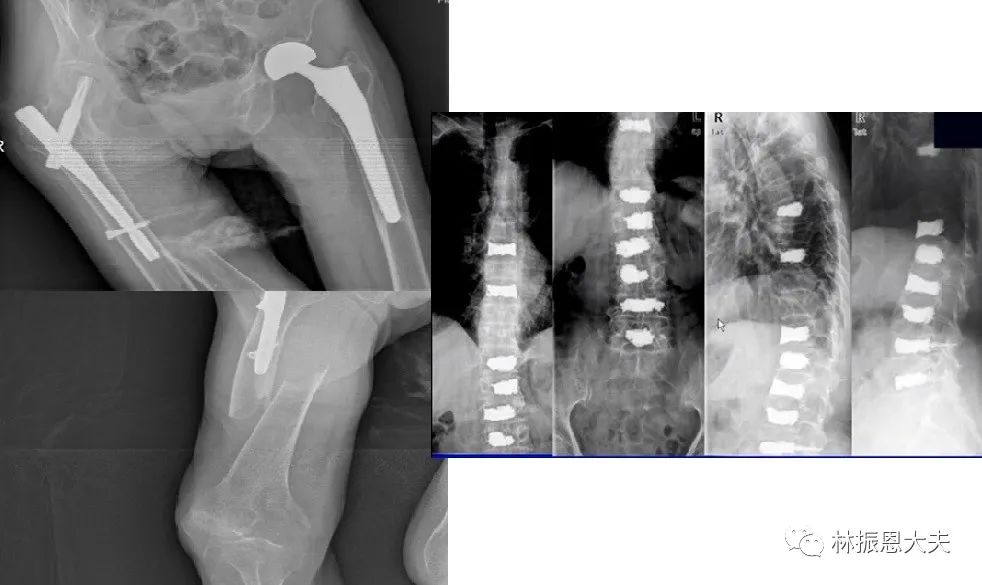

说到钙片,首先要认识是否需要补钙,正常的儿童和成人通过均衡饮食、晒晒太阳,能够提供必要的钙补充与利用,不需要补钙,但对于营养不良(挑食)、骨折后的患者、老年人骨质疏松反复骨折、反复手术,的确需要补钙。